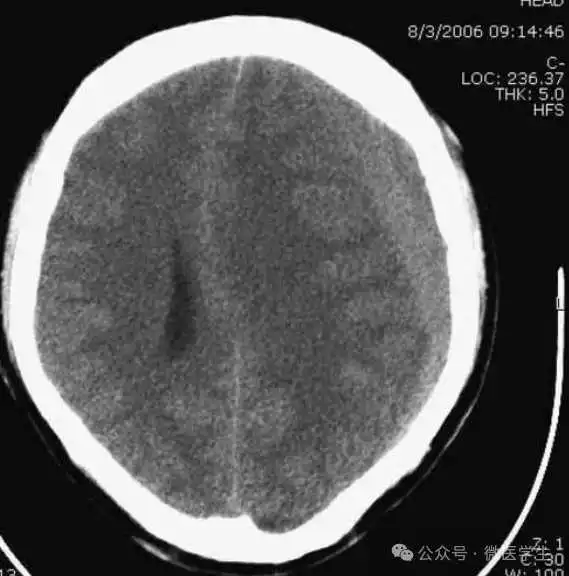

由额、颞、枕叶构成,两侧侧脑室体部之间为透明隔,外侧为尾状核和体部。侧脑室后角(枕角)可不对称,室内可见脉络丛钙化。中线处可见大脑纵裂池和大脑镰。

内侧壁侧脑室体部被胼胝体分开,侧脑室体部的外方为顶叶,顶枕沟及中央沟将大脑为为额、顶、枕叶。

在胼胝体和侧脑室上方,大脑镰自前向后贯穿中线。白质部分为半卵圆中心,额叶范围缩小,顶叶所占比例扩大,枕叶基本消失。

- 半卵圆中心:位于胼胝体上方,由左右大脑半球髓质形成的有髓纤维,对称位于大脑镰两侧区域。

已近颅顶,大脑镰清晰可见,其旁的脑灰质和脑沟十分清楚。顶叶较小,额叶较小。

- 放射冠:是内囊到大脑皮质间的放射状纤维白质。